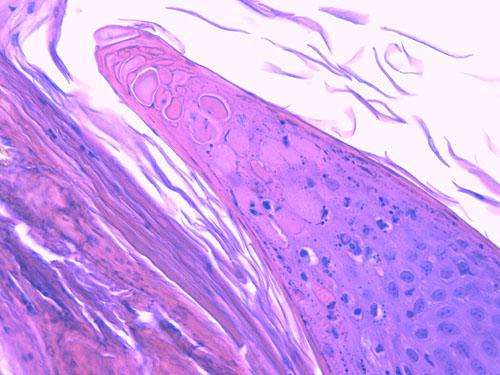

Photo 11 (Hémalun Eosine X 100): l’épiderme et les infundibula folliculaires

sont hyperplasiques et hyperkératosiques. Notez la projection papillaire à la marge d’un ostium folliculaire.

Le derme montre une inflammation péri-vasculaire.

Légendes de la Photo 11 :

- Flèche turquoise : projection papillaire de l’épiderme hyperplasique se formant à la marge d’un ostium folliculaire

- Ronds marrons : tiges pilaires

- Ovales turquoises vides : follicules pileux, infundibula hyperkératosiques (orthokératose)

- Double flèche orange : épiderme (portion non kératinisée)

- Double flèche verte : derme

- Étoiles rouges : infiltrat inflammatoire dermique péri-vasculaire